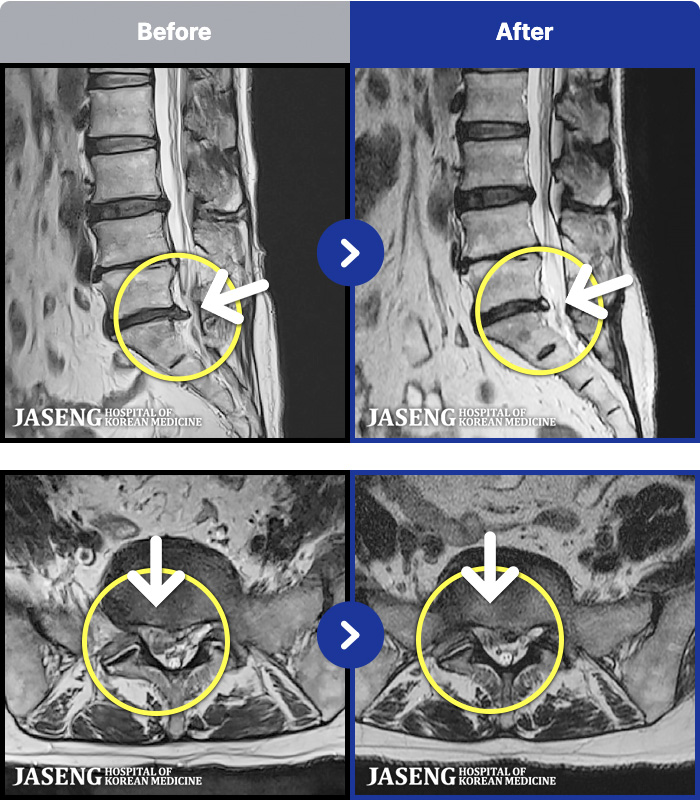

MRI ġ

56 MRI ũ ʸ Ȯϼ.